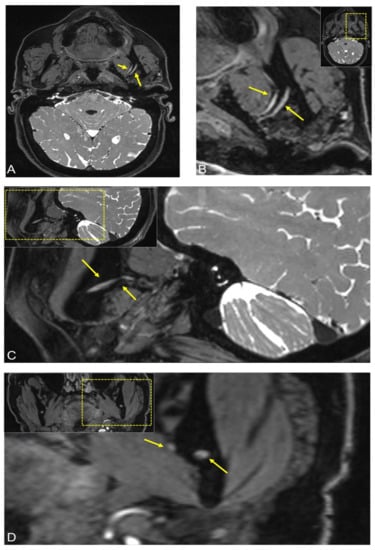

2.1. Case 1

2.2. Case 2